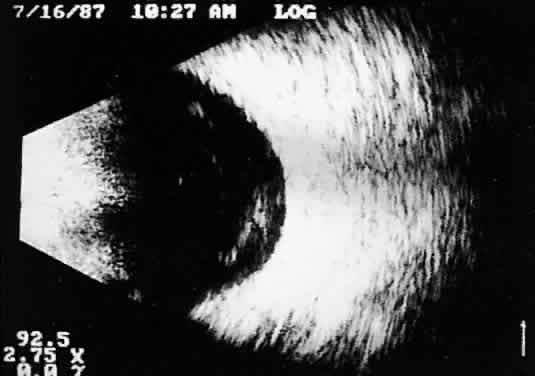

Tumors with great acoustic heterogeneity, such as choroidal hemangiomas, where adjoining cell and tissue layers have marked differences in acoustic impedance, create large echo amplitudes at each interface. These tumor types have typical high internal reflections at each major interface. These high internal reflections make the lesions appear solid white in B-scan displays and produce highamplitude spikes during A-scan imaging (Fig. 12).

Fig. 12. Contact B-scan and simultaneous A-scan: choroidal hemangioma. Ultrasonically heterogeneous tissue shows strong reflectivity at all levels, appearing white in B-scan gray scale.